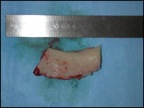

Photo prélèvement osseux crânien

On ne prélève que la couche externe de l’os, en aucun cas le cerveau n’est vu pendant l’intervention. Il reste protégé par la partie interne de l’os crânien.